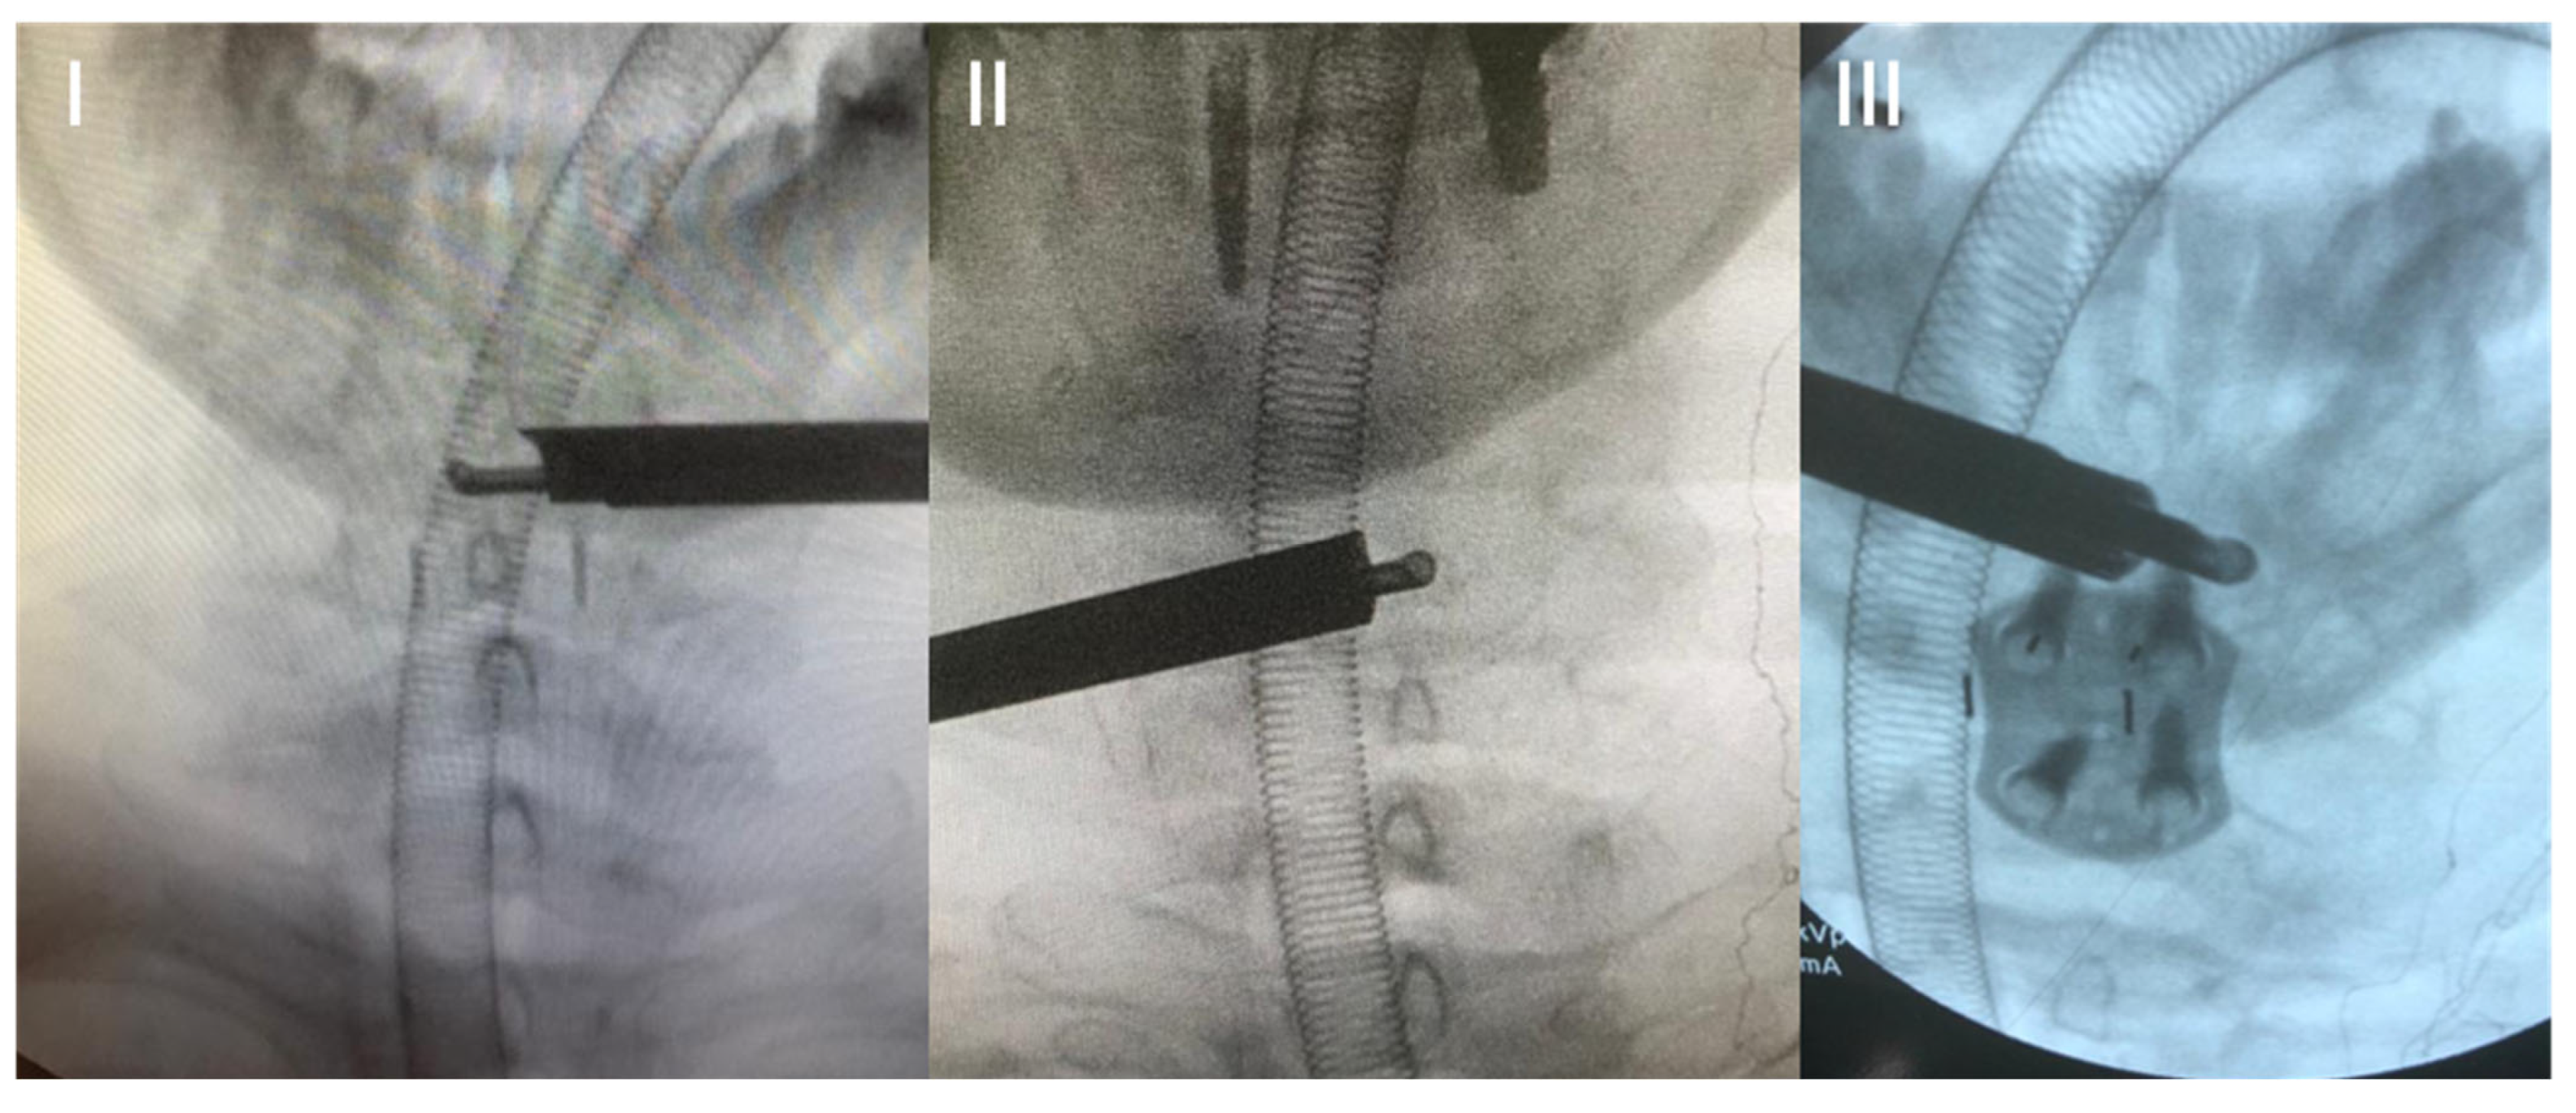

2. Surgical Technique